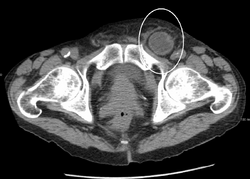

An incarcerated inguinal hernia as seen on CT

By far the most common hernias (up to 75% of all abdominal hernias) are inguinal hernias, which are further divided into the more common indirect inguinal hernia (2/3, depicted here), in which the inguinal canal is entered via a congenital weakness at its entrance (the internal inguinal ring), and the direct inguinal hernia type (1/3), where the hernia contents push through a weak spot in the back wall of the inguinal canal. An indirect inguinal hernia and a direct inguinal hernia can be distinguished by their positioning in relation to the inferior epigastric vessels. An indirect hernia is situated laterally to these vessels, whereas a direct hernia is positioned medially to them. Inguinal hernias are the most common type of hernia in both men and women. In some selected cases, they may require surgery.

There are special cases where a direct and indirect hernia appear together. A pantaloon hernia (or saddlebag hernia) is a combined direct and indirect hernia when the hernial sac protrudes on either side of the inferior epigastric vessels.

Additionally, though very rare, two or more indirect hernias may appear together such as in a double indirect hernia.[26]